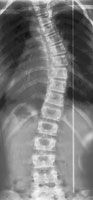

Возможность использования топографического мониторинга состояния больных сколиозом взамен рентгена была изучена на основе клинического материала школы-интерната №133 для детей больных сколиозом г.Новосибирска, где, начиная с 1995 года, проводились ежегодные обследования на ТОДП постоянного контингента больных параллельно с рентгеном. Среди больных по характеру течения заболевания выделены 3 группы: СФ - стабильная форма сколиоза, УПФ - умеренно прогрессирующая, БПФ - быстро прогрессирующая форма. Пример наблюдения больной с быстро прогрессирующей формой сколиоза приведен на рисунках ниже.

9,0 лет 10,4 лет 10,8 лет 11,4 лет 12 лет

PTI=1,0; Cobb=10° PTI=1,3; Cobb=17° PTI=1,9; Cobb=23° PTI=2,9; Cobb=38° PTI=3,6; Cobb=55°

За трехлетний период наблюдения в возрасте с 9 до 12 лет основная правосторонняя грудная дуга по углу Кобба спрогрессировала с 10 до 55°, т.е. средняя скорость прогрессирования составила 15° в год. Общий индекс нарушения формы дорсальной поверхности туловища PTI изменился с 1,0 (граница нормы и умеренно выраженных отклонений) до 3,6 (значительное отклонение). Следует обратить внимание, что в начале наблюдения туловище больной имело хороший баланс во фронтальной плоскости (вертикальная ось, проходящая через вершину межъягодичной складки, проходит также и через C7), а с возраста 10,8 лет стало явно нарастать нарушение баланса с отклонением туловища вправо, т.е. в сторону выпуклости основной дуги. Приведенный пример убедительно демонстрирует наглядность топографических данных и их большую информативность для решения задачи неинвазивного мониторинга состояния больных сколиозом.